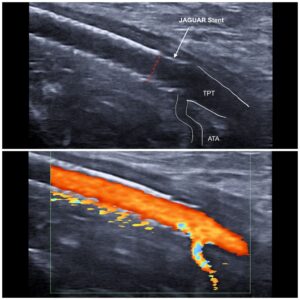

Caso de la semana: Recanalización compleja de oclusión de stent femoropoplíteo con rescate distal mediante stent JAGUAR (Balton)

Caso de paciente con diabetes avanzada y enfermedad arterial que acudió por fracaso de injerto y herida isquémica en pie derecho.